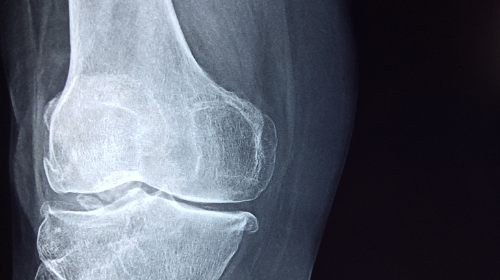

La artrosis de rodilla es una enfermedad degenerativa crónica caracterizada por el desgaste progresivo del cartílago articular. Produce dolor mecánico, rigidez, inflamación y pérdida de función, pudiendo generar deformidades en varo o valgo. El tratamiento se adapta a la etapa de la enfermedad, desde medidas conservadoras hasta cirugía protésica.

La artrosis de rodilla es una enfermedad degenerativa crónica caracterizada por el desgaste progresivo del cartílago articular. Produce dolor mecánico, rigidez, inflamación y pérdida de función, pudiendo generar deformidades en varo o valgo. El tratamiento se adapta a la etapa de la enfermedad, desde medidas conservadoras hasta cirugía protésica.